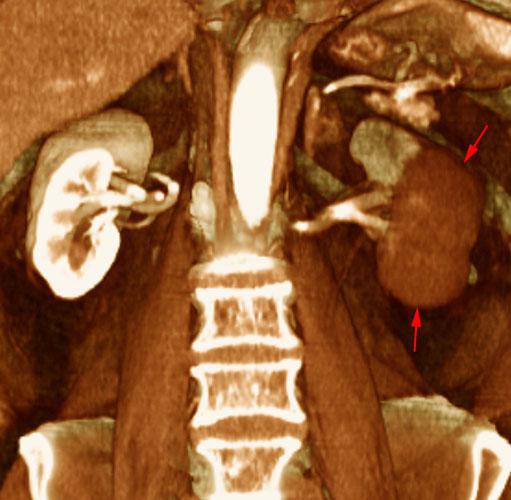

Infartos renales múltiples